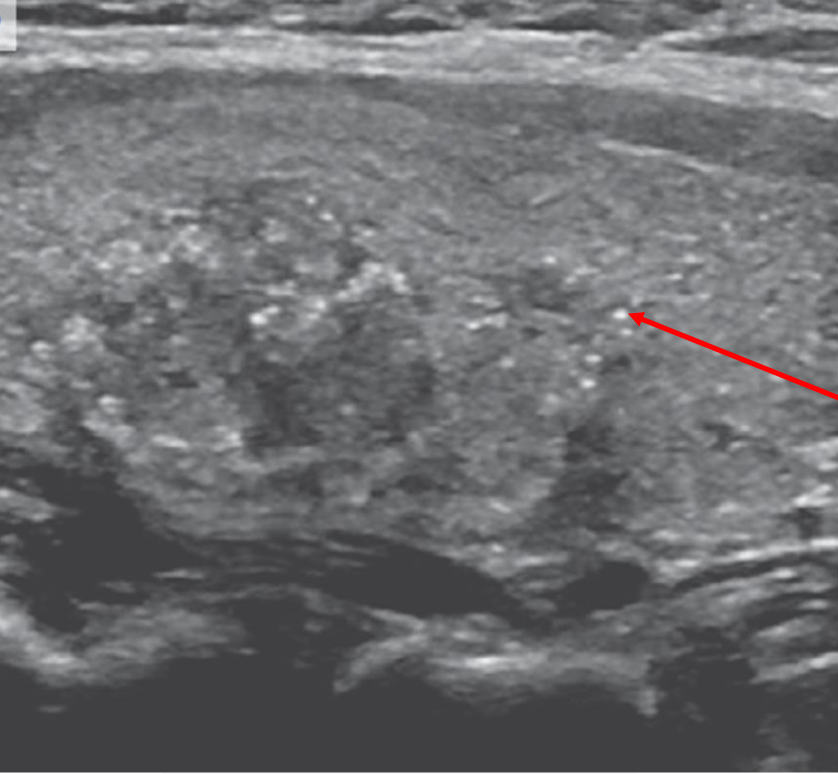

40 year old healthy female for a routine exam

You see & palpate a 2 cm right-sided neck lump:

non-tender, well-circumscribed & freely moveable

no palpable nodes or other masses

The rest of your exam is negative

- characterize this ultrasound finding. What’s next to do?

2 cm solid nodule